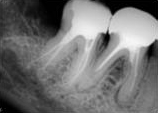

antes depois